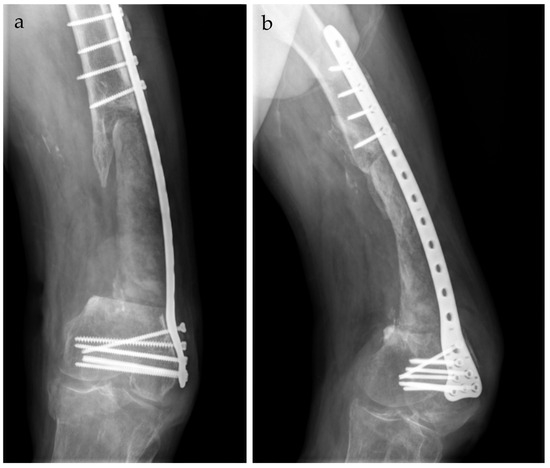

The Use of the Masquelet Technique in the Treatment of Pathological Distal Third Femoral Fracture Secondary to Chronic Osteomyelitis

2. Case Report